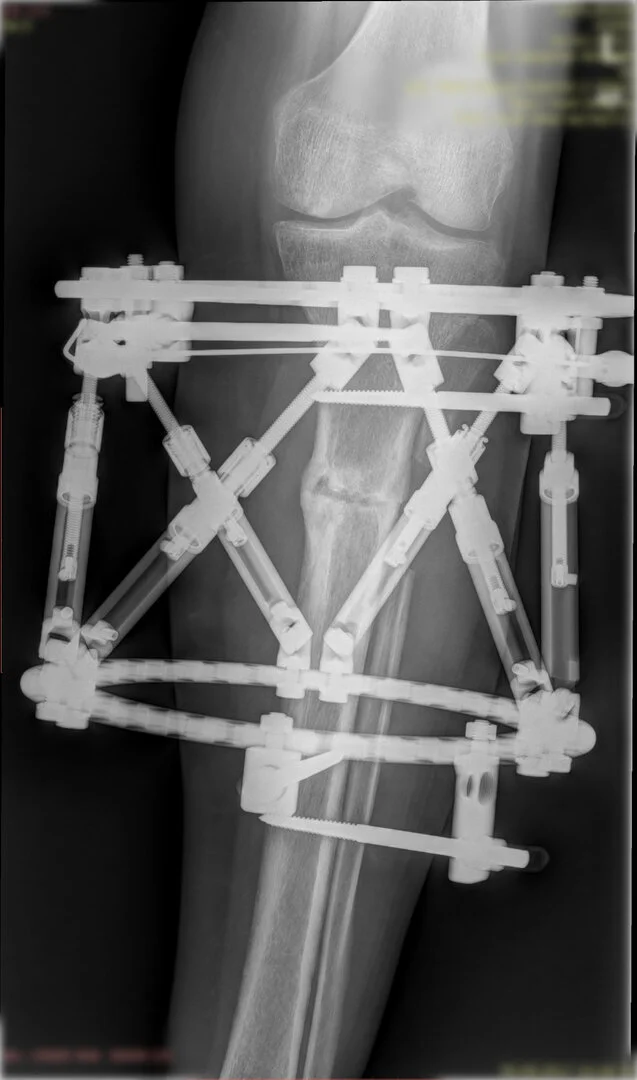

Deformitenin yeri ve miktarına bağlı olarak bilgisayar destekli sirküler eksternal fiksatör ile tedrici düzeltme yapılabilir. Bu sistemin avantajı düzeltme esnasında sistemle oynayarak yeni düzenlemeler yapmanıza izin vermesidir.

Bu ameliyat öncesi bir deformite analizi yapılıp hangi kemikte, normalden ne kadar sapma olduğu tespit edilir. Daha sonra bu kemiğe yine ostetomi yapılarak bu anormal sapma düzeltilir.  Bu düzeltme plak-vida veya intramedüller çivi ile akut olarak düzeltilebileceği gibi bilgisayar destekli sirküler eksternal fiksatör ile tedrici olarak ta yapılabilir. Hangi yöntemin hangi hasta için uygun olacağına hasta özelinde karar veriyoruz, ne tür cerrahi tedavi olması gerektiğini danışabilirsiniz.

Görüntüleri büyütmek için üzerine tıklayınız.